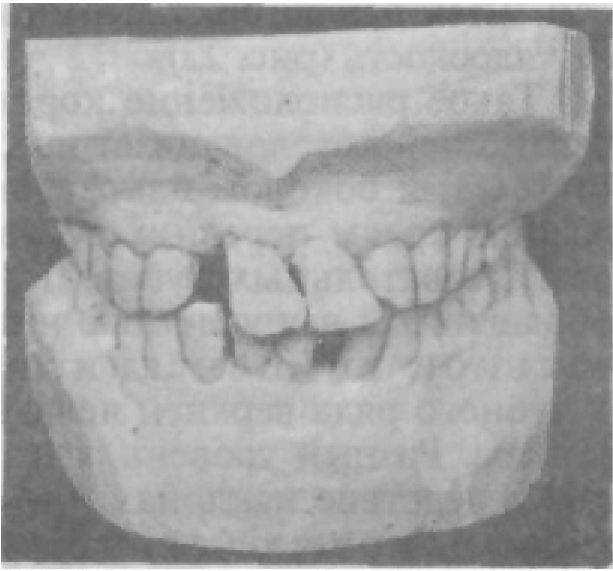

Характерным признаком построения зубных рядов является то, что срединные продольные межбугорковые фиссуры жевательных зубов и середины режущих поверхностей передних зубов нижней челюсти проецируются на середину альвеолярных гребней. Группа передних зубов верхней челюсти составляет исключение из этого правила — их режущие поверхности сдвинуты в губную сторону (рис. 19). Эти топографические взаимоотношения коронок с центром альвеолярного отростка служат ориентиром при создании искусственных зубных рядов. Отклонение зуба от этого расположения (рис. 20) является одним из симптомов, позволяющих в комплексном анализе субъективных ощущений, анамнестических данных установить, отклонился ли зуб в горизонтальном направлении от своего первоначального положения в дуге или это его индивидуальное (но аномалийное) положение. Различают смещение зуба (зубов) в интактном зубном ряду, смещение зуба (зубов) при дефектах зубных рядов и смещение зуба вследствие его неправильного прорезывания (дистопия зуба). Направления смещения зуба в сформированной зубочелюстной системе разнообразны и зависят от характера и направления действия сил жевательного давления: расположен ли зуб в зоне фиксированного функционального центра или в зоне нефункционирующей группы зубов. Принято различать смещения зуба: 1) вестибулярно или орально; 2) медиально или дистально; 3) в вертикальном направлении: супраокклюзионно (ниже окклюзионной плоскости зубного ряда) или инфраокклюзионно (выше окклюзионной плоскости зубного ряда); 4) поворот зубов вокруг вертикальной оси (ротация), ротационное смещение.

Смещение зуба в любом направлении — симптом заболевания зубочелюстной системы. Выявление этого симптома требует от врача проведения дополнительных методов исследования, установления механизмов смещения, а по результатам всего комплекса диагностического процесса — установления диагноза. Так, вестибулярное смещение центральных резцов с образованием между ними промежутка (ложная диастема); смещение передней группы зубов, супраокклюзионное положение одного из резцов с различной степенью ротации патогномонично для ряда заболеваний — пародонтоза, пародонтита (рис. 21).